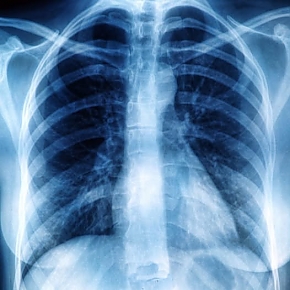

A röntgen-mellkas esetében szemből és oldalról is készül felvétel, a vizsgált terület nagyobb, így átfogóbb képet nyújt a mellkas minden struktúrájáról, és ezáltal a tüdőn, a szíven, az érhálózaton, a csontokon és a légutakon lévő elváltozások is kimutathatóak. Azért is indokolt a mélyrehatóbb vizsgálat, mert több mint 10 ezer tüdődaganatos megbetegedést regisztráltak tavaly. Nagyon fontos, hogy időben felismerjék a daganatot, mert ezáltal jelentősen javul a gyógyulási esély.